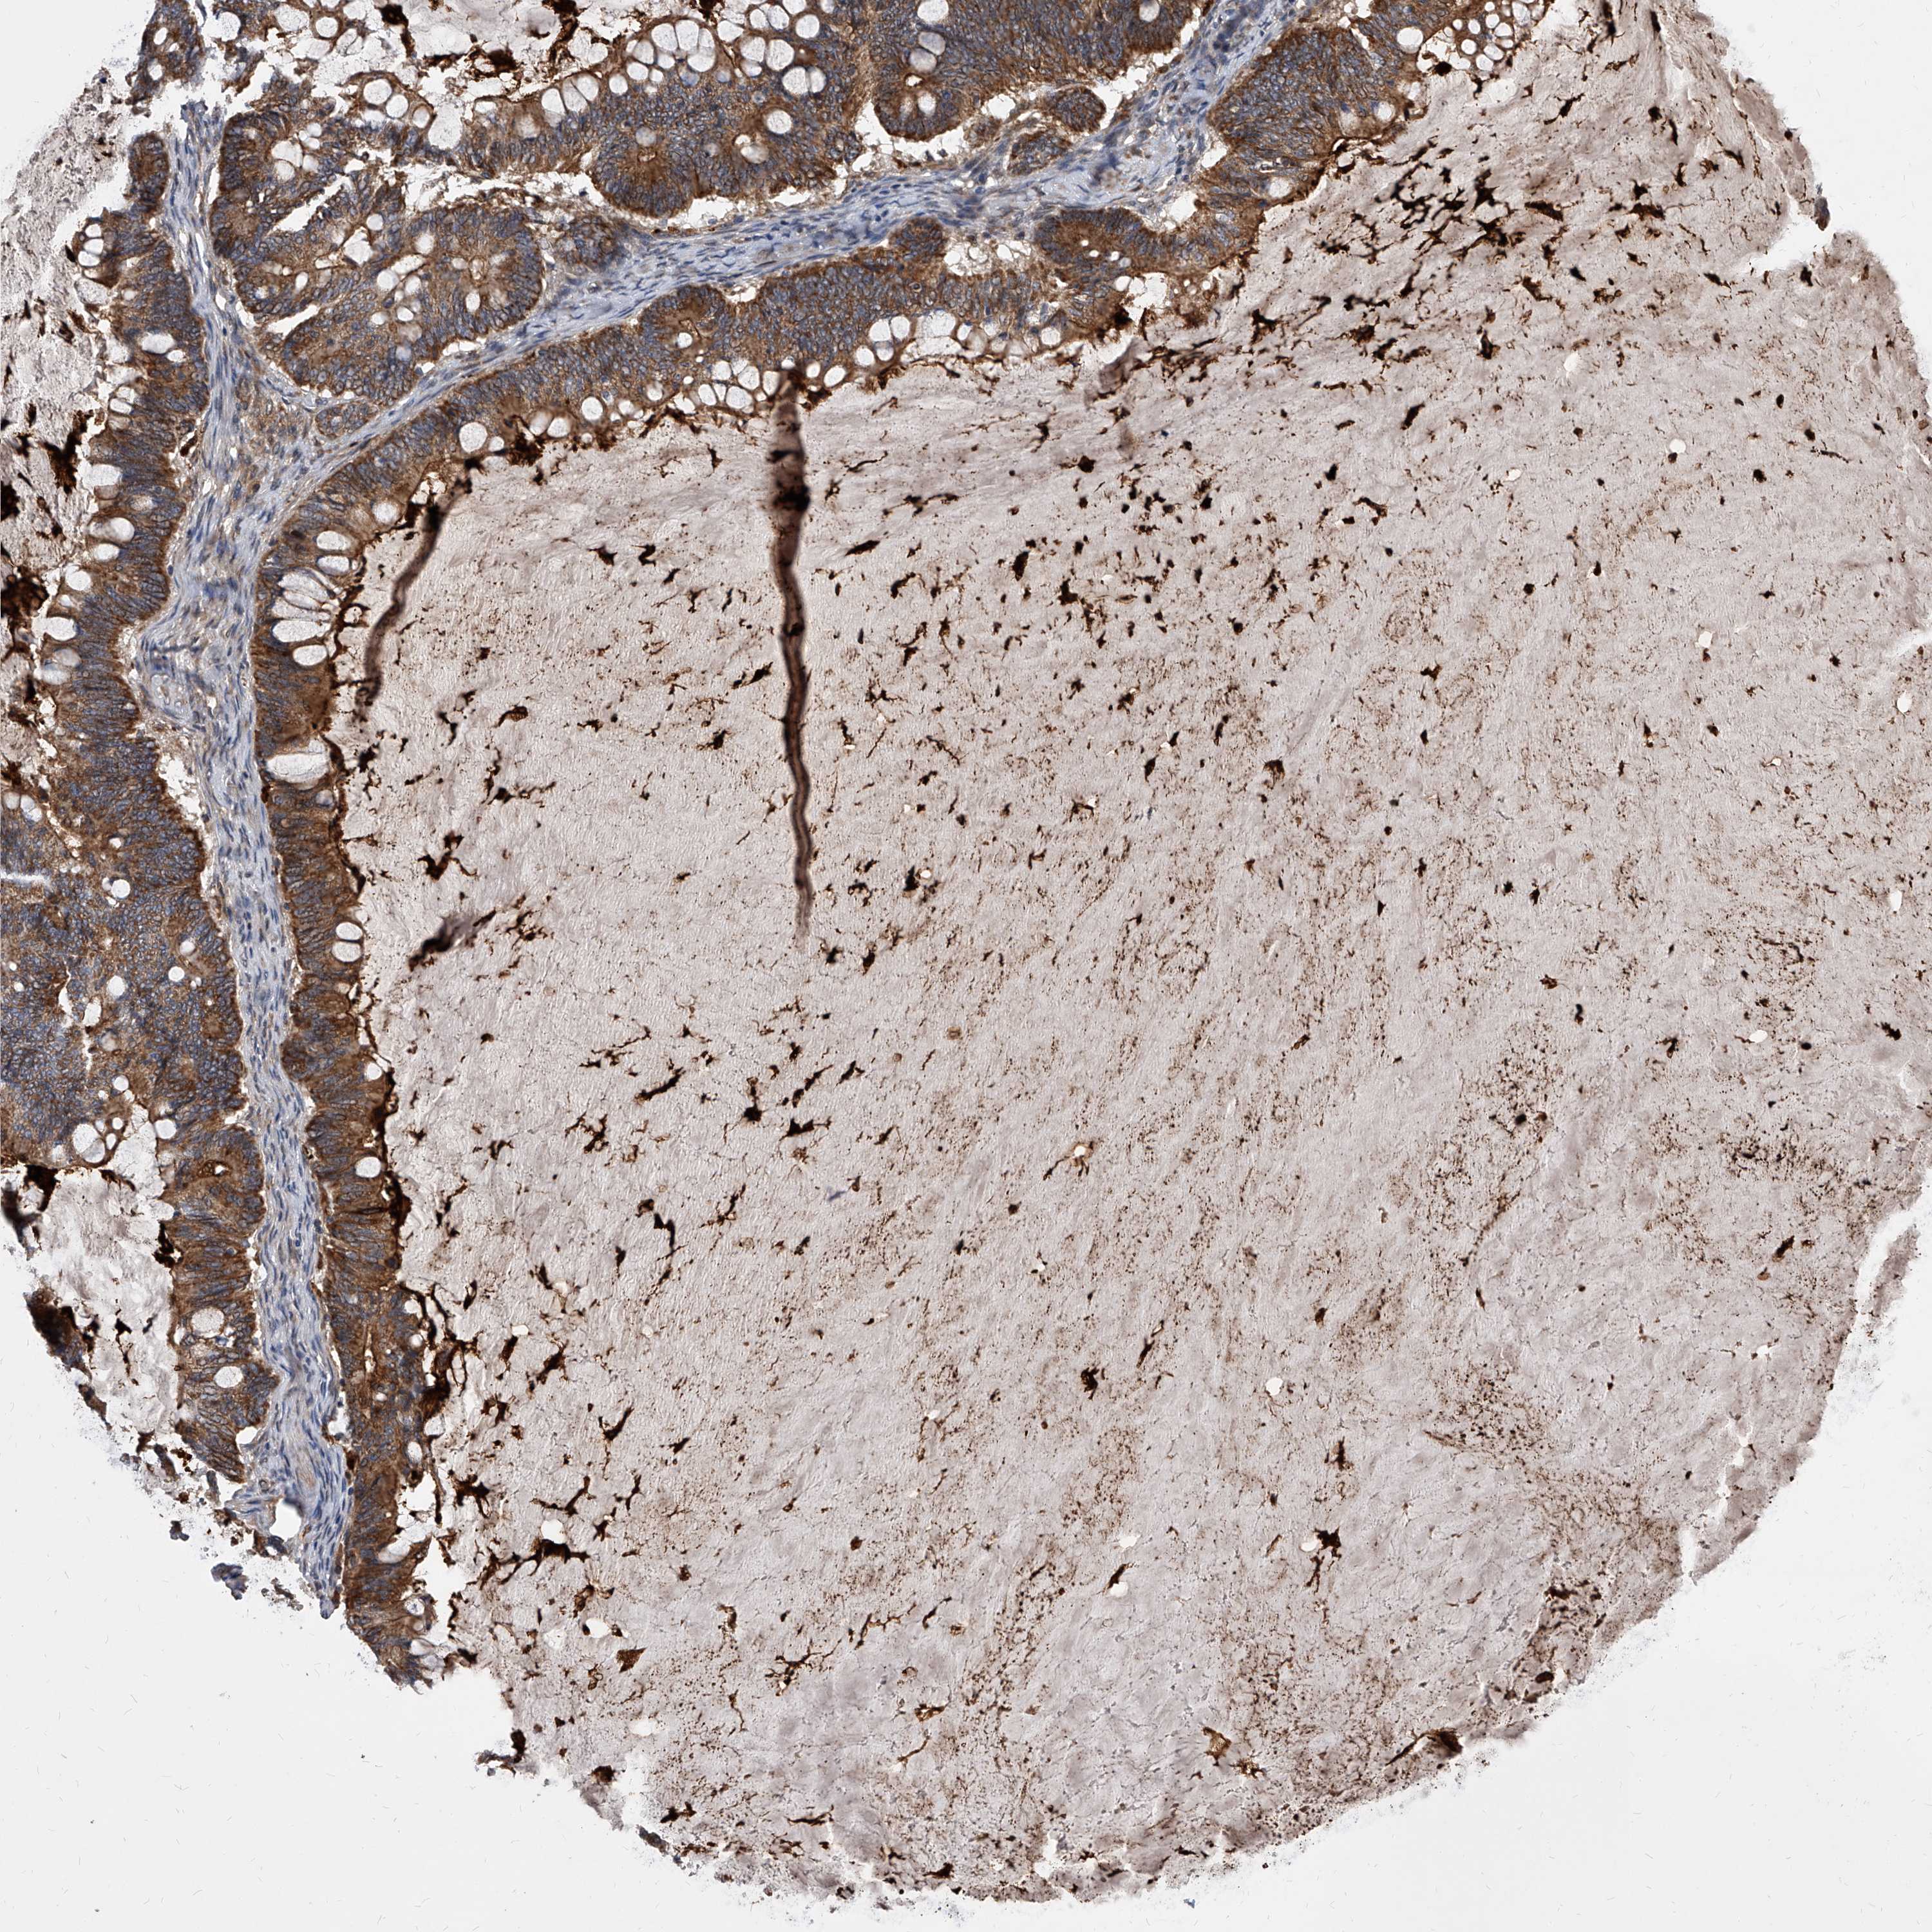

OVARIAN CANCER - Protein expressioni

A mouse-over function shows sample information and annotation data. Click on an image to view it in a full screen mode. Samples can be filtered based on level of antibody staining by selecting one or several of the following categories: high, medium, low and not detected. The assay and annotation is described here.

Note that samples used for immunohistochemistry by the Human Protein Atlas do not correspond to samples in the TCGA dataset.

Antibody stainingi

Antibody staining in the annotated cell types in the current human tissue is reported as not detected, low, medium, or high, based on conventional immunohistochemistry profiling in selected tissues. This score is based on the combination of the staining intensity and fraction of stained cells.

Each image is clickable and will lead to virtual microscopy that enables deeper exploration of all samples and also displays staining intensity scores, fraction scores and subcellular localization as well as patient and tissue information for each sample.

Antibody HPA029242

Staining

High

Medium

Low

Not detected

Intensity

Strong

Moderate

Weak

Negative

Quantity

>75%

75%-25%

<25%

None

Location

Nuclear

Cytoplasmic/membranous

Cytoplasmic/membranous,nuclear

Cystadenocarcinoma, serous, NOS

Carcinoma, endometroid

Cystadenocarcinoma, mucinous, NOS

Carcinoma, NOS